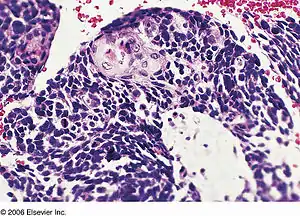

| Combined small cell lung carcinoma containing a component of squamous cell carcinoma | |